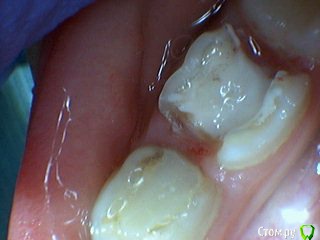

Давлетшин Опубликовано 29 декабря, 2017 Поделиться Опубликовано 29 декабря, 2017 (изменено) Друзья. Расскажите, не поменялось ли ваше отношение к пульпотеку и пр.Почему пломбы поверх пульпотеку такие ужасно жёлтые? Что сделать можно. Или что я делаю не так? "Друзья" так приятно перед новым годом. К пульпотеку не поменялось (устраивает вполне) , к пульподенту скептическое отношение, хоть и тоже работаю. Пломбы сразу желтые или через полгода - год- два? Очень тяжело что то советовать он лайн не видя как человек работает. В фото первая цифра пациент, вторая-третья номер зуба, четвертая порядок фото. Я после наложения пульпотека , стараюсь убрать излишки, или аккуратно на устья каналов накладываю, в пульповую камеру СИЦ, и сверху пломбу, Убрать излишки и со стенок, аккуратно в том числе и бором. В третьем клиническом случае, неудача. Зуб удалил сам же через 3 месяца. причину вижу в том что на рентгене не увидел (или так сделали снимок?) вертикальный тип рассасывания практически до бифуркации., может и потому что ребенок ОЧЕНЬ плохо сидел. За фото не пинайте сильно, не инстаграмм все таки,да и тяжело ребенка лечить и фотки делать. или наоборот пинайте может лучше начнем фоткать. P.s. Добавлю протокол как лечу с пульпотеком, хр.фибр.пульпит1. анестезия2. кофер ( если дает)3. раскрытие кариозной и пульповой камеры4. удаление коронковой пульпы маленьким эскаватором, я стараюсь "отрубать" пульпу5. остановка кровотечения сухим ватным шариком, 0,5-1-2 минуты6. пульпотек на устья7 СИЦ в пульповую камеру8 со стенок остатки пульпотека соскребаю бором фиссурным , цилиндрическим, там же фальц9. Пломба. может что то и зыбыл ну и оценка только позитивная перед НГ Изменено 29 декабря, 2017 пользователем Давлетшин 2 Ссылка на комментарий